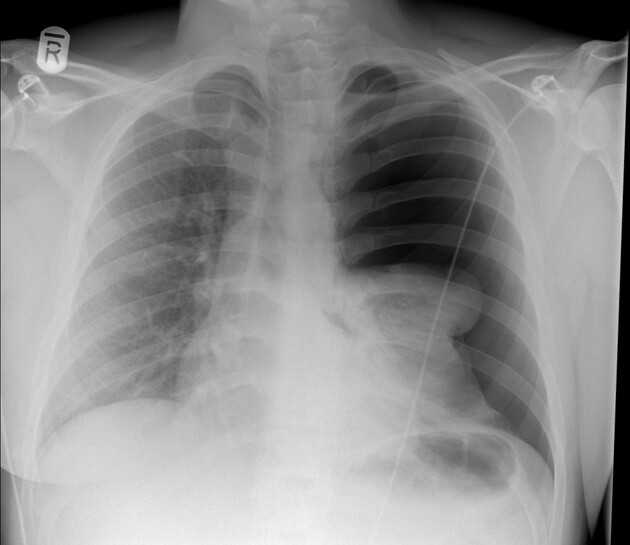

Chest x-ray findings are nonspecific in an asthmatic attack. It should not be used routinely in the assessment of asthma but consider CXR in any patient presenting with an atypical history or with atypical findings on examination. CXR if atypical symptoms, may show hyperinflation. The chest x-ray may help rule out acute infection as the cause of an acute attack.

The findings are in going with COPD. Haematocit can be raised in COPD. Chest X-ray is not required for diagnosis of COPD, and repeated CXR is unnecessary, unless other diagnosis are being considered (most importantly, lung cancer or bronchiectasis).

If a chest X-ray is ordered, these are the findings:

- Hyperinflated lung fields

- > 7 posterior ribs seen

- Flattened diaphragms

- Small heart

- May see bullae